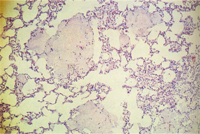

組織病變: 許多肺泡可見顆粒狀、泡沫狀、嗜酸性之無組織結構物質不規則散佈於肺泡中,間 雜肺泡巨噬細胞,少量嗜中性球,圍小支氣管及圍血管淋巴球及漿細胞增生,肺泡第二 型細胞增生(圖2,3)。